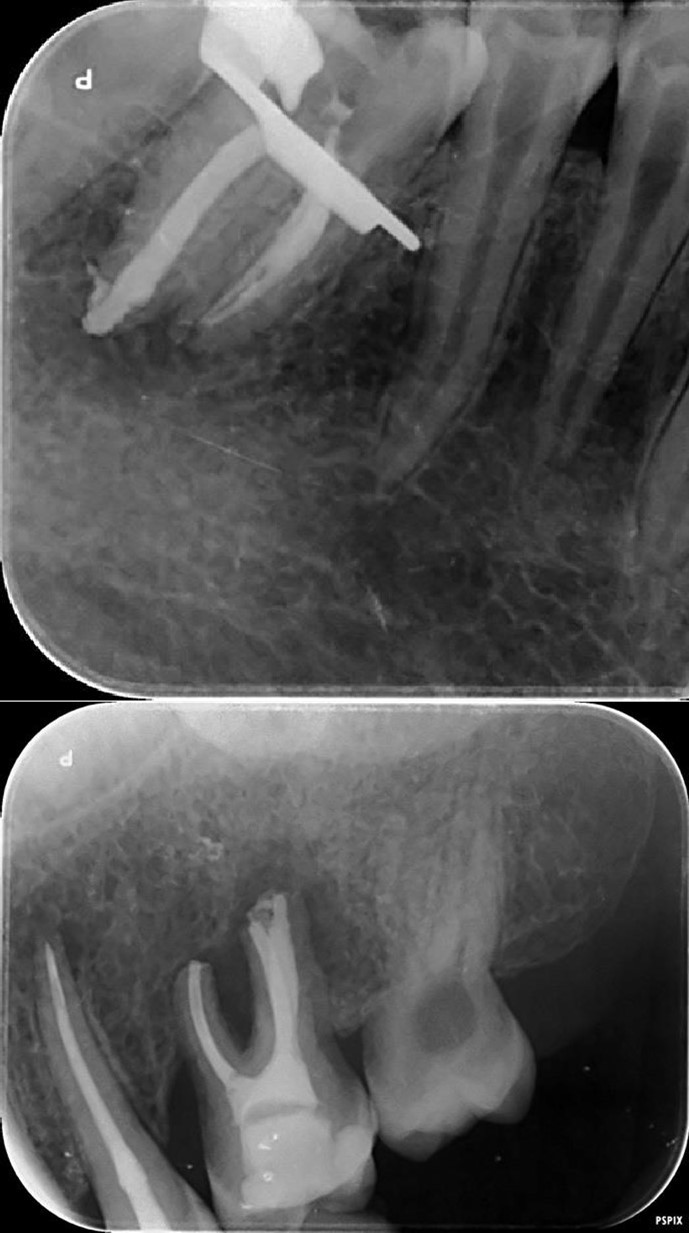

Periapical radiography (phosphorus number 2 plaque and X-MIND® Unity; Acteon) and cone-beam computed tomography (X-MIND® 3D; Acteon) (80 × 80, 150 Micron) were performed and showed periapical lesions on teeth 14, 15, 16, 24, 25, 26, 35, 36, and 46, as well as advanced endo-perio lesions on teeth 26 and 16. orthopantomogram (X-MIND® 3D; Acteon) and bitewings (phosphorus number 2 plaque and X-MIND® Unity; Acteon) also showed wide pulp chambers and roots canals. Figure 1, Figure 2

Figure 1.1 and 2 show a wide pulp chamber, root canals, and several restorations.

Figure 2.2. 3, 4, and 5 show periapical lesions on teeth 15, 16, 24, 25, 26, 35, 36, and 46.